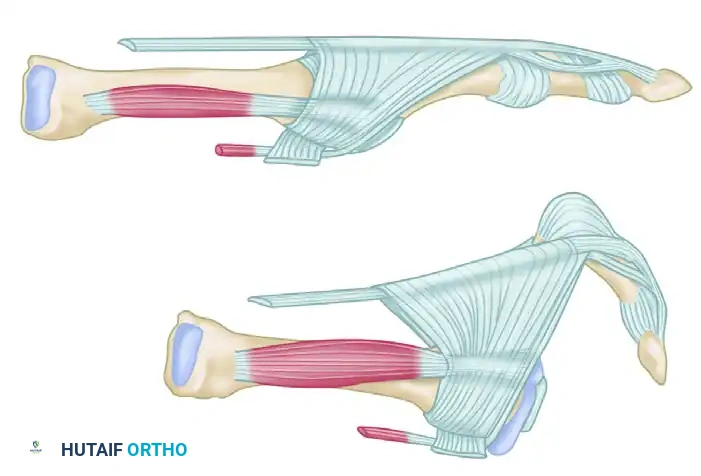

The most critical and consistent physical finding in MTP instability is a positive Lachman Test (Drawer Sign) of the MTP joint. This test assesses the integrity of the plantar plate and collateral ligaments.

To perform the Lachman test:

1. The examiner stabilizes the metatarsal head securely with one hand.

2. The other hand grasps the base of the proximal phalanx.

3. A pure dorsal translation force is applied to the proximal phalanx while maintaining the joint in a neutral alignment.

(Starting position for the Lachman test, demonstrating stabilization of the metatarsal and grasping of the proximal phalanx.)

(Positive Lachman test demonstrating significant dorsal translation and subluxation of the proximal phalanx, indicative of plantar plate incompetence.)

(Alternative view: Starting position for examination of MTP joint stability.)

(Alternative view: Positive test with visible and palpable dorsal subluxation of the joint.)

A positive test is characterized by excessive dorsal translation, a "mushy" or absent endpoint, and reproduction of the patient's pain. Range of motion testing will typically reveal limited plantar flexion compared to the contralateral, healthy toe, secondary to dorsal contracture.